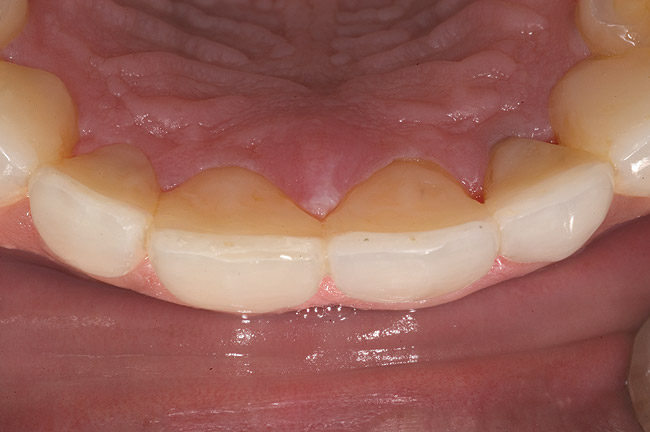

Figure 6  1:1 view demonstrating severe loss of tooth structure due to palatal erosion.

Figure 6

Figure 7  Palatal surface showing loss of form due to enamel dissolution.

Figure 7